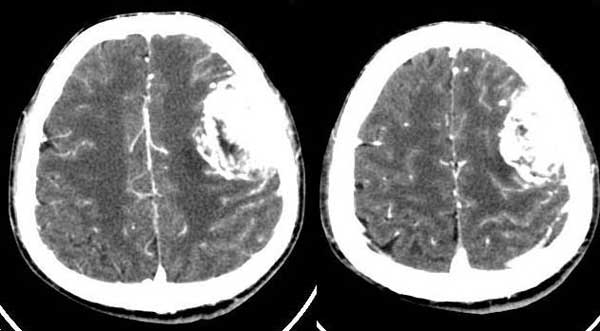

皮质塌陷,增强比较明显,有一定的占位效应,脑内水肿不显著,脑外病变可肯定,考虑脑膜瘤,但平扫密度较低,颅骨改变也不明显,确实应排除一下脑血管病.

本例我首先考虑脑膜瘤,但其具有形态不规则、密度不均匀、有明显的坏死液化、没有完整和明显的包膜、且呈明显不均匀性强化等诸多恶性特点,应该首先考虑恶性脑膜瘤(但颅骨只有轻微受压而没有明显的受浸润破坏现象也不太支持)。

还有不支持的地方,比如那么大地肿瘤而瘤周水肿不明显。所以,我第2考虑海绵状血管瘤。建议mri检查。

支持脑膜瘤的地方:强化明显,水肿轻,中线移位不明显(但颅顶层面有大脑镰限制也不好说),相应脑灰质受压内移。

不支持脑膜瘤的地方:每个层面肿块与颅骨内板几乎都呈锐角,相邻颅骨无明显骨质改变。

我还是考虑左侧额顶叶胶质瘤。